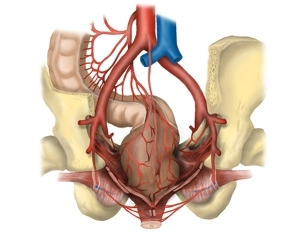

Vasos

![Vasos]()

- Anastomosis entre el territorio de la arteria mesentérica superior (A. colica media) y la arteria mesentérica inferior (A. colica sinistra) cerca de la flexura cólica izquierda (arcada de Riolan)

- Suministro del hemicolon izquierdo, del colon sigmoide y del recto superior por la A. mesentérica inferior y las que salen de ella A. colica sinistra, Aa. sigmoideae con la arcada de Drummond, A. rectalis superior.

- Suministro del tercio superior del recto por la A. rectalis superior, que se divide dorsalmente en dos ramas terminales, del tercio medio por la A. rectalis media (pareada, cada una como rama de la A. iliaca interna) y del tercio inferior por la A. rectalis inferior (pareada, cada una como rama de la A. pudenda interna de la A. iliaca interna). Las Aa rectales mediae discurren en los llamados ligamentos laterales del recto y se seccionan durante la escisión mesorrectal total.

- Drenaje venoso del hemicolon izquierdo a través de venas homónimas en el territorio de la vena porta

- Drenaje venoso de los dos tercios superiores a través de la V. mesenterica inferior (territorio de la vena porta) y del tercio inferior a través del área de drenaje de la V. cava inferior